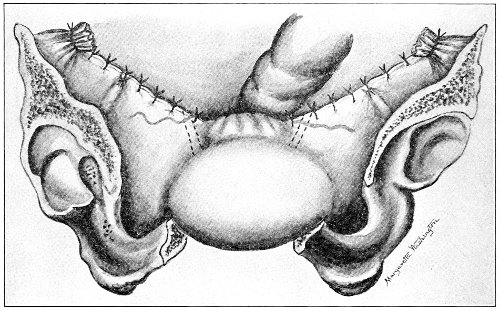

An accurate knowledge of the anatomy and mechanism of the female perineum is essential to an understanding of the nature and treatment of injuries to this structure. The anatomical structures lying between the anus behind and the symphysis pubis in front are those that most directly interest the gynecologist. Proceeding from 57 below upward, we find the following structures lying in superimposed planes: the skin, the superficial fascia, the deep layer of the superficial fascia, the transversus perinæi and the sphincter vaginæ muscles, the anterior layer of the triangular ligament, the posterior layer of the triangular ligament, the levator ani muscle (Fig. 19).

The injuries to the perineum that may result from childbirth are classified according to the position or the direction and extent of the laceration. They are as follows: slight median tear; median tear involving the sphincter ani; tear in one or both of the vaginal sulci; subcutaneous laceration of the muscles and fascia.

All these injuries demand operative treatment. The operation for the repair of injuries to the perineum is called perineorrhaphy. It is called immediate or primary, intermediate, and secondary perineorrhaphy, according to the time after the receipt of the injury at which the operation is performed. The primary operation is done during the first twenty-four hours. The primary operation should always be performed. A careful inspection of the perineum and the posterior vaginal wall should always be made after labor, and any laceration should be repaired within twenty-four hours. The advantages of the primary operation are many. The parts are usually so numb that it is not necessary to administer an anesthetic. No denudation is necessary, and therefore no tissue need be sacrificed. The woman is spared the pain and discomfort of granulation and cicatrization.

The bad results that follow neglect of the primary operation are very numerous, and will be studied hereafter. The injured muscles retract, and, being functionally useless, undergo atrophy, and when finally repaired never possess their former strength. Involution in the vagina and the uterus may be arrested, and all the disasters incident to subinvolution may appear. Vaginal and uterine prolapse occur; the natural supports of the 63 vagina and uterus become stretched, and, though afterward the perineum may be restored, yet it may be found impossible to retain the uterus in its proper position. It is always good surgery to repair an injury as soon as possible.

When practicable, a certain amount of preparation of the patient should be made before the operation of perineorrhaphy. This is most easily effected before the intermediate and secondary operations. The vagina and the vulva should be sterilized, and the intestinal tract should be emptied. Thorough evacuation of the bowels is most important when the sphincter ani has been injured, because it is desirable, after operation for this lesion, that the bowels should not be moved for five or six days. A saline purgative should be administered on an empty stomach about five hours before the operation, and a rectal injection of soap and water should be administered about one hour before the operation. Whatever purgative be employed, it should be administered at such a time that its action shall have ceased by the time of the operation. If this precaution is not observed, there may be a discharge of feces that will infect the wound and interfere with the manipulations.

For operation upon the perineum the woman should be placed in the dorso-sacral position (Fig. 1, page 23).

The intermediate operation is performed during the granulation period—ten days or two weeks after labor. At this time the raw surfaces are covered with granulation-tissue and bathed with pus. The edges of the wound and the surrounding tissue may be hard and swollen from infiltration with inflammatory products. In the intermediate operation it is necessary to administer an anesthetic or to anesthetize the parts locally with a 10 per cent. solution of cocaine.

All cicatricial tissue, granulation-tissue, and rough edges should be scraped away with the knife, the scissors, or the curet. The raw surfaces should be thoroughly 64 washed with a 50 per cent. solution of peroxide of hydrogen and a 1:1000 solution of bichloride of mercury. The sutures should then be introduced.

The secondary operation is performed at any time after cicatrization has occurred—often many years after the receipt of the injury. This operation is at present one of the commonest in gynecology, because the injury is not detected, is neglected, or is improperly repaired after labor. In the secondary operation an anesthetic is necessary. The mucous membrane must be removed or denuded on the posterior wall and about the mouth of the vagina, in order that the lacerated structures may be brought again in apposition. The denudation is best made by means of scissors curved on the flat (Figs. 24 and 25).

The strip of mucous membrane to be removed is picked up with a tenaculum (Fig. 26) or with tissue forceps 65 (Fig. 27); the scissors are placed with the blades parallel to the surface to be denuded, and the strip is cut away evenly, in one piece if possible. A similar contiguous strip is removed, and so on until the necessary surface is bare. Sponges in holders (Fig. 28) or continuous irrigation may be used to remove blood.

The sutures may be fastened by passing the ends through a perforated shot which is slipped down to the line of union and compressed by the shot-compressor (Fig. 32). All blood should be carefully removed from the surfaces that are brought together. The sutures should only be sufficiently tense to produce accurate apposition. A light gauze drain should be introduced in the vagina, and should be removed in forty-eight hours. Afterward one vaginal douche of about a quart of warm bichloride solution (1:2000) should be administered every day. After the douche the labia should be separated and the vagina carefully dried by cotton held in dressing-forceps. Except in those cases in which the sphincter ani is involved, the bowels may be moved on the second or third day. The woman should stay in bed for two weeks, at the end of which time the sutures should be removed. 67 She should avoid heavy lifting, long standing, and bicycle- or horseback-riding for two months after the operation. Constipation should always be avoided. Coitus may be resumed six weeks after operation.

Slight Median laceration of the Perineum.—In this injury the tear takes place through the fourchette. Posteriorly it may extend as far as the sphincter ani muscle. Upward it may extend for an inch up the posterior vaginal wall. The appearance of this tear is shown in Fig. 33. It will be noted that, as this tear takes place in the median line, none of the muscles that support the perineum are involved, nor are the planes of fascia injured. The perineum is slightly split, and the insertions and origins of the muscles and the fascia are slightly separated. The supporting structures of the perineum and the pelvic floor are, however, uninjured.

Fig. 33.—Recent slight median laceration of the perineum: sutures introduced.

If this tear is detected after labor, it should be closed by the immediate operation. A slight tear involving chiefly the cutaneous aspect of the perineum should be closed by three or four sutures introduced from the outside, as in Fig. 33. The needle should be introduced about a quarter of an inch from the edge of the wound. It should not be passed parallel with the plane of the lacerated surface, but should be swept outward and then inward toward the 68 angle at the bottom of the tear (Fig. 34). It may either emerge at the angle and be re-introduced, or it may be passed directly through to the skin-margin on the opposite side of the wound. If the suture is passed in this way, there will be perfect apposition throughout the whole surface of laceration. If the sutures are improperly passed, there may result only apposition of the skin-edges.

Fig. 34.—Diagram representing the correct and the incorrect method of passing the suture for closure of slight perineal laceration.

If the laceration extends up the posterior vaginal wall, two sets of sutures must be introduced—one on the vaginal aspect of the tear, and one on the skin aspect (Fig. 35).